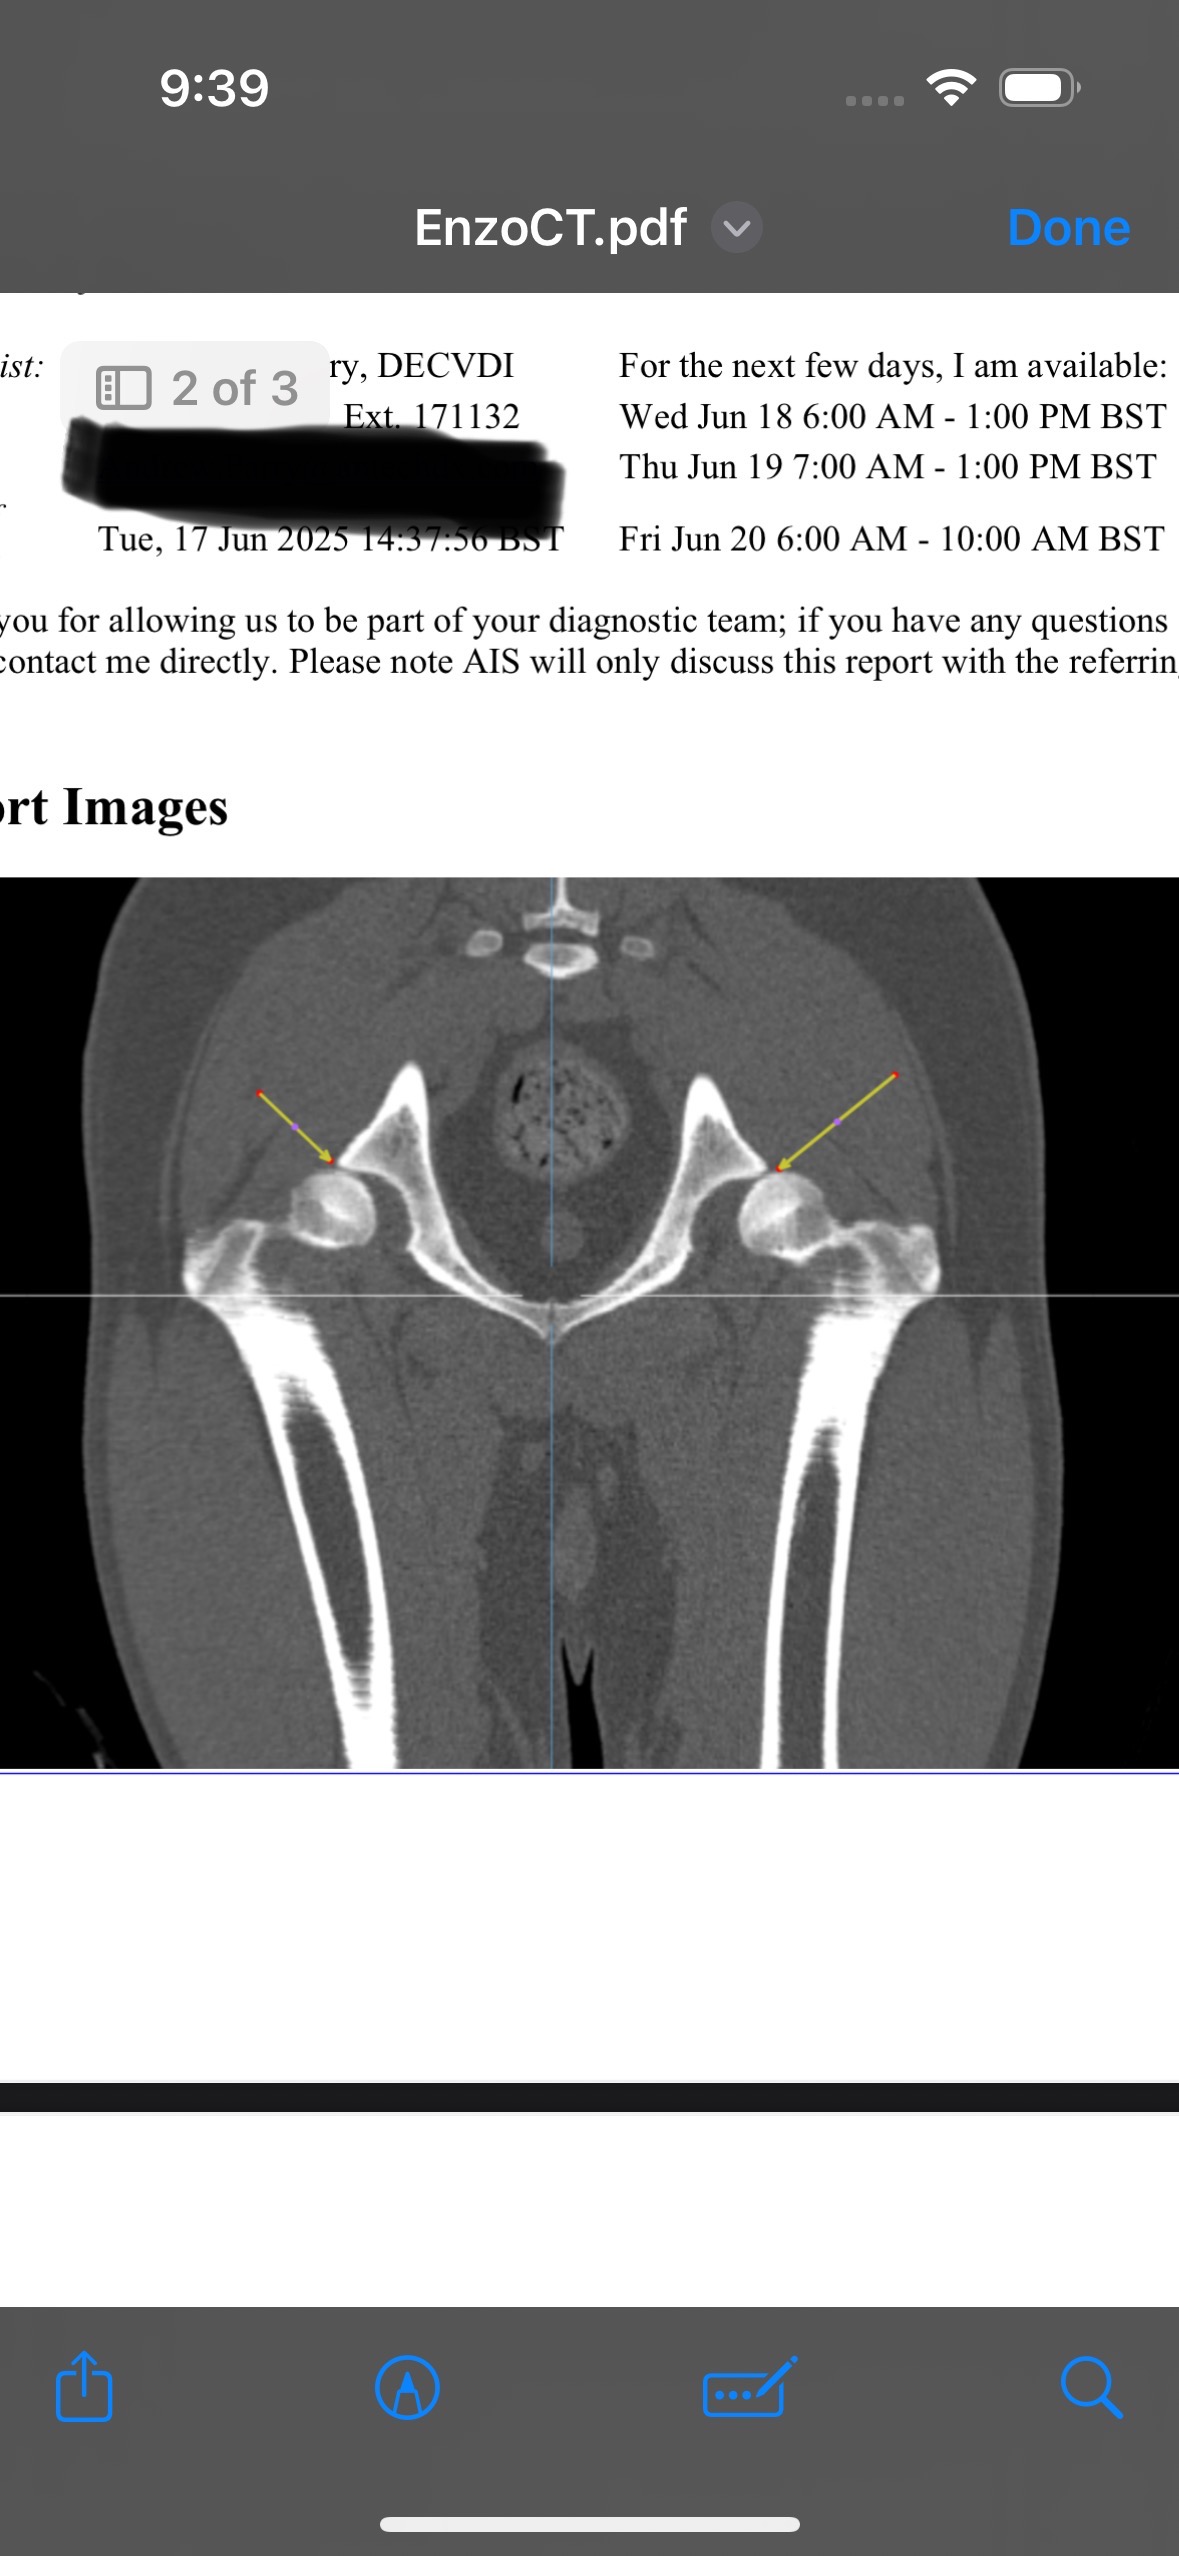

After months of backwards and forwards to vets and physio appointments, we unfortunately received the bad news that Enzo has bilateral hip dysplasia and needs total hip replacement surgery on both to give him back his quality of life. Unfortunately he hasn’t responded well to pain relief and it is recommended that the surgery is the best option to give him the pain free life he deserves. The poor puppy will have been in pain all his life.